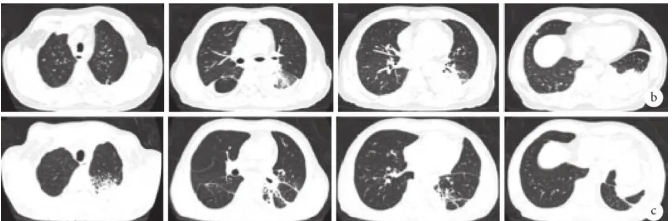

患者中年男性,急性病程,因“发热、咳嗽半月”于2024-12-25入院。事业单位退休人员。患者于半月前无明显诱因出现发热,热型不详,伴咳嗽,少量黄黏痰,无胸痛、明显气促、咯血、腹泻等不适,于2024-12-17外院住院查胸部CT示左肺下叶感染性病变可能性大,双肺新发多发结节,右肺下叶结节切除术后改变。痰病原学提示:嗜肺军团菌。考虑诊断为社区获得性肺炎,经验性予哌拉西林他唑巴坦+莫西沙星抗感染治疗,症状无明显好转;于2024-12-22复查胸部CT示左下肺病变较前有所加重(图1a),遂至我院住院诊治。

图1 不同时期典型胸部CT像

a. 2024-12-22

经过治疗后患者症状及体征明显好转,复查感染指标明显下降,复查胸部CT示左下肺病灶较前吸收减少(图1b),遂予出院。院外继续予伏立康唑片200 mg q12h口服规律治疗。出院期间均规律至门诊随访,其间查伏立康唑血药浓度(谷浓度):0.57 μg/mL(2月7日),10.5 μg/mL(3月26日),复查胸部CT示左下肺部病灶基本完全吸收(图1c)。

b. 2025-01-08;c. 2025-02-05

复查PET-CT:(1)原左下肺实变代谢弥漫性增高灶,体积较前增大,代谢增高(图1d),余双肺多发结节较前明显缩小、数量较前减少,代谢基本降低至本底水平,综上考虑为TM感染治疗后活性较前好转;(2)原左侧腋窝、左锁骨下、双侧肺门、纵隔、左侧内乳区、肝胃间隙、脾胃间隙、胰头周围、腹主动脉两旁、右侧髂血管旁,右侧腹股沟区多发高代谢淋巴结,体积较前缩小,部分较前消失,代谢较前减低,考虑为TM感染治疗后活性部分受抑,但仍有活性残余;(3)右后下胸膜单发高代谢结节体积较前缩小,代谢较前明显减低原肝脏、脾脏及胸5左侧附件多发高代谢结节较前消失,综上所述考虑为TM感染治疗后活性基本受抑。

d. 2025-04-07

该患者最终确诊为:(1)嗜肺军团菌肺炎;(2)播散性TSM(肺、肝、脾、淋巴结、骨髓);(3)抗IFN-γ自身抗体综合征;(4)2型糖尿病;(5)右下肺恶性肿瘤手术切除。经过治疗后,患者无发热,症状好转,予出院。院外继续使用左氧氟沙星口服抗嗜肺军团菌,伏立康唑抗TM,定期监测伏立康唑血药浓度。随访2个月未见复发,于2025年6月24日复查胸部CT示原左下肺病灶基本吸收(图1e)。

e. 2025-06-24